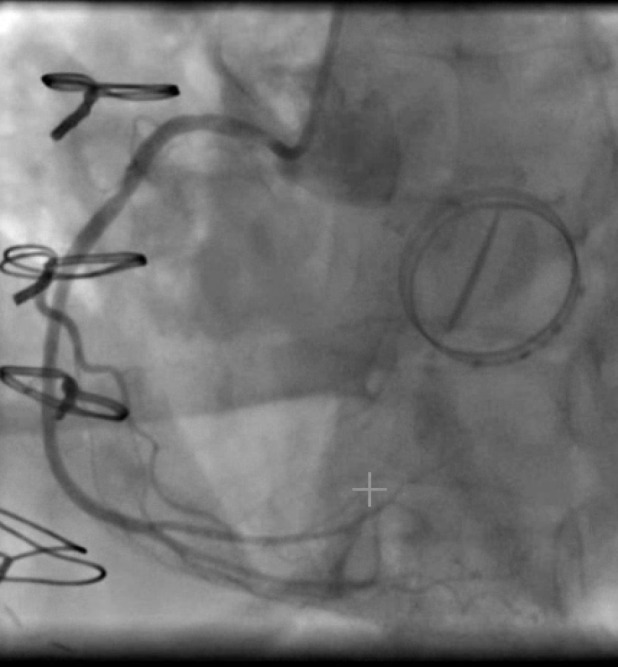

Case presentation: A 58-year-old female presented with New York Heart Association (NYHA) Class II symptoms resulting from severe, highly eccentric anterior mitral regurgitation from a bio-prosthetic valve. She had preserved ejection function and a total calcium score of zero. This patient underwent a re-do mechanical mitral valve replacement. Two days post-surgery, she was brought to the catheterization laboratory with signs and symptoms suggestive of an inferior myocardial infarction (MI) and complete heart block (CHB). Her symptoms and ST changes resolved immediately after the introduction of angiographic contrast. Angiography revealed no occlusion in the right coronary artery (RCA).